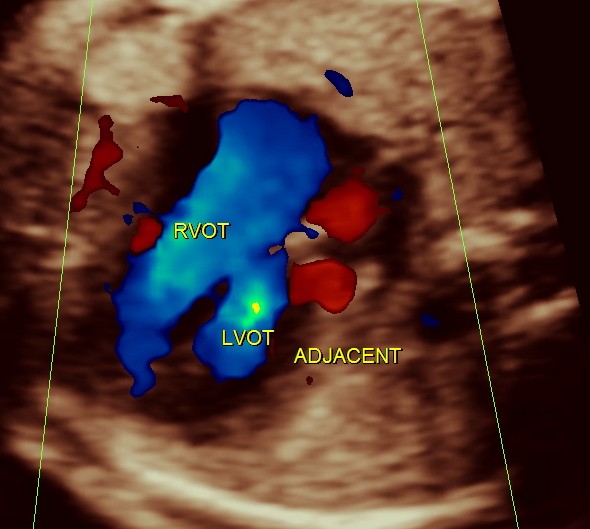

generally colour flow imaging is not said to be very helpful

the following 3 D reconstructed image shows the parallel flow of the great arteries